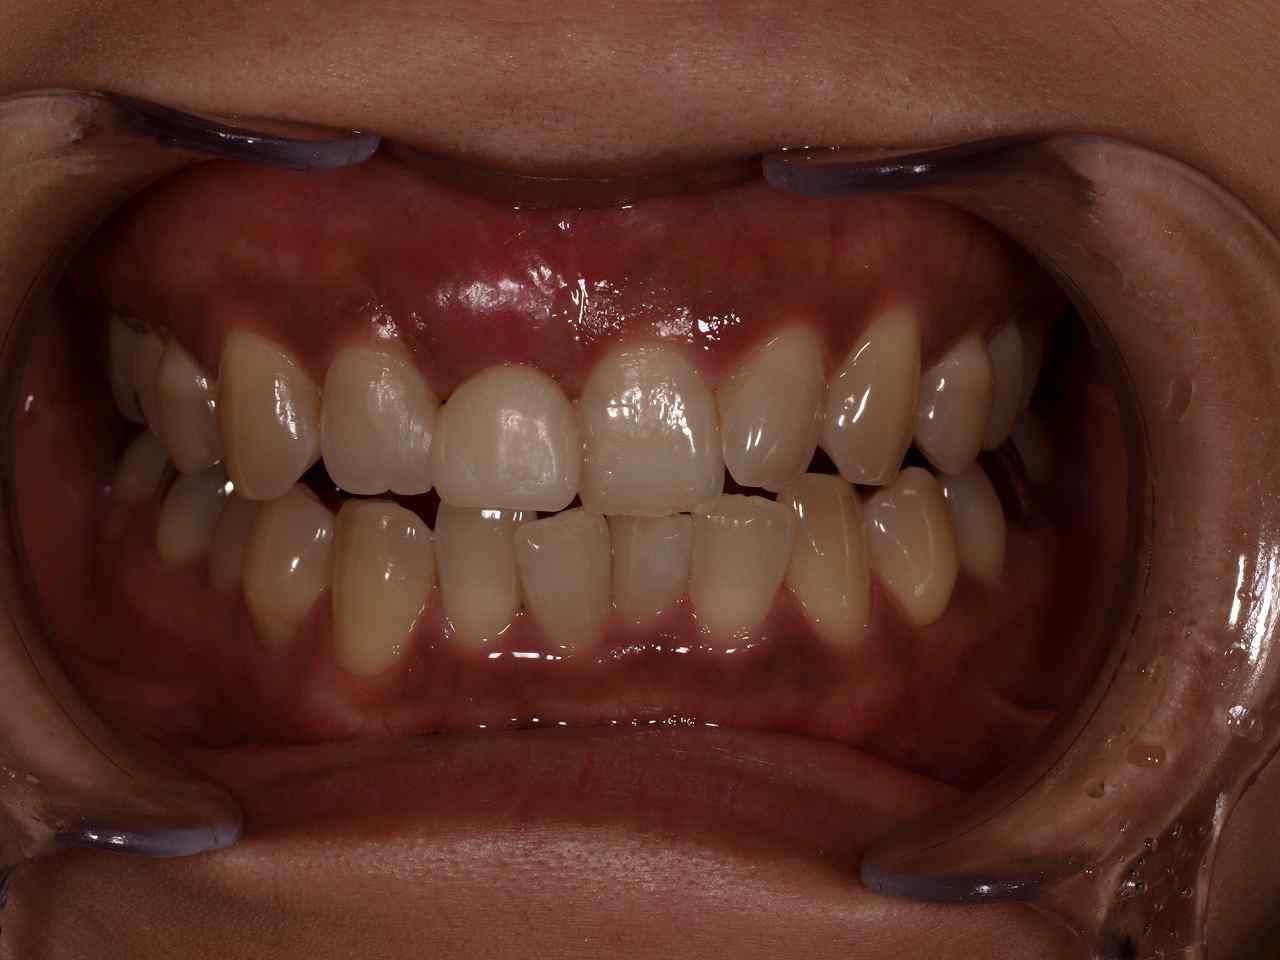

初診時になります

このような仮歯が入っていました

2週間後にはこのようになります

このように普通歯を抜歯したら歯茎は下がるのですが、、、

即時インプラント埋入することによって、歯茎が上がってきています